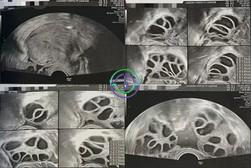

促排第 11 天 — 几乎所有卵泡已达目标大小;准备取卵

超声结果

右侧卵巢:卵泡大小 21,20,20,21,19,19,19,18,18,18,17,16,15,14 mm → 共 14 个卵泡

左侧卵巢:卵泡大小 22,20,20,20,20,20,19,19,18,17,17,17,17,16 mm → 共 14 个卵泡

在本病例中,卵巢刺激反应良好。卵泡从最初的小尺寸逐渐发育,到第 11 天时已有大量卵泡达到适宜大小(18–22 mm)。雌激素水平也持续升高,提示卵泡已准备好接受触发针注射和取卵。